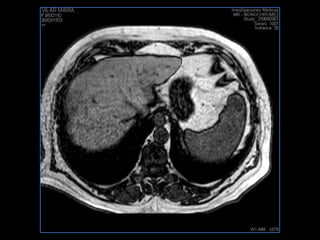

PROTOCOLO hígado graso AXIAL in phase y out phase AX T1 y AX fat sat +SAG T2  CON   GADOLINIO :  COR T1+AX T1(DIN) SAT: NO  FASE: RL THK: 4MM  COIL:  GAP: (FACTOR 1.4)  FOV: 40 CM NEX:2 SINCRONIZACION RESPIRATORIA EN 3 O 4 CICLOS ALE